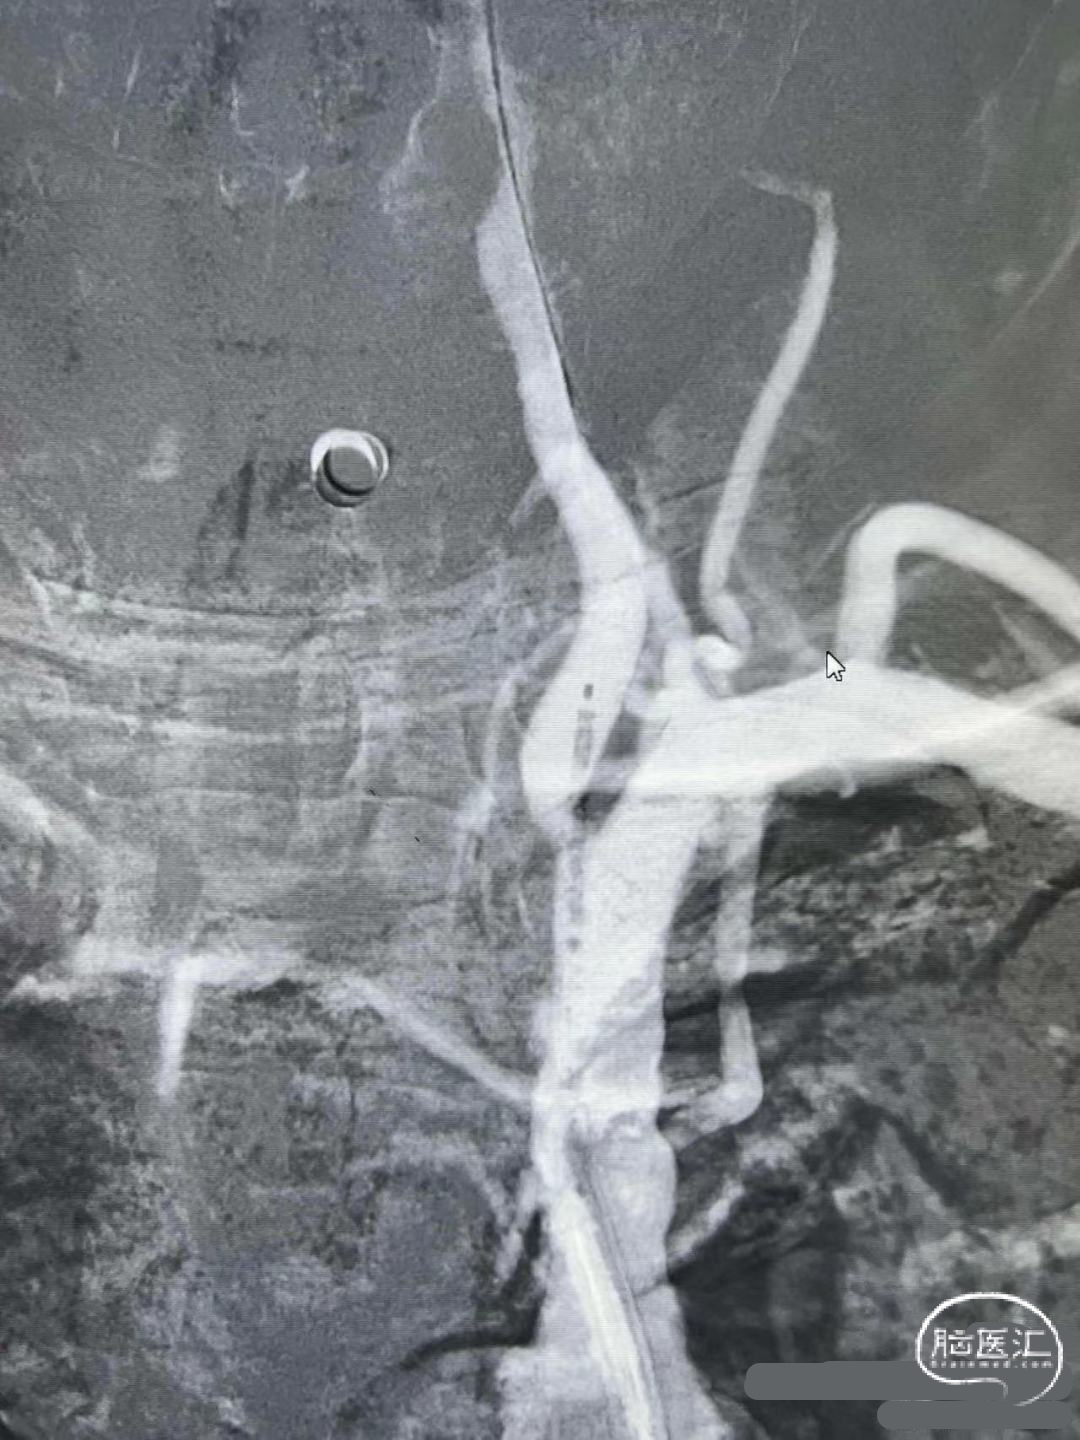

支架释放:

释放4mm*25mm Neurohawk取栓支架,可见支架显影良好,支撑性好,远端打开良好。中间导管跟上抽吸-SWIM技术。

操作要点:

固定支架推送杆,缓慢回撤支架微导管。

支架回撤:

借助支架锚定,跟进中间导管至接触血栓,SWIM技术取栓一次,恢复血流。